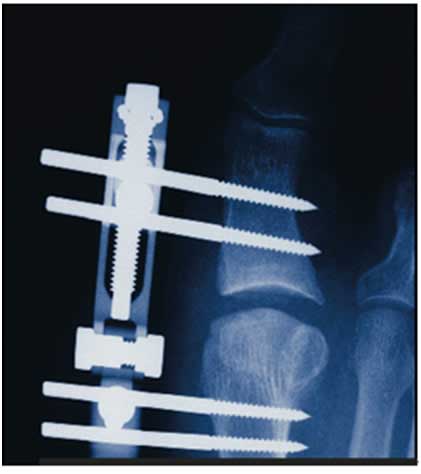

報(bào)告中,Dr. Devon針對(duì)保守方案無(wú)效后的手術(shù)備選方案也進(jìn)行了詳細(xì)的闡述,考慮到患者還年輕,為盡量挽救患者的跖趾關(guān)節(jié),手術(shù)方案建議首選“借助微型軌道外固定器進(jìn)行關(guān)節(jié)切開(kāi)術(shù)和關(guān)節(jié)分離”(下圖示),